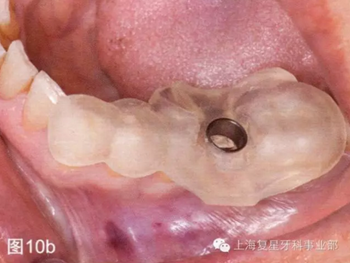

第二天患者就診進(jìn)行手術(shù)。用0.12%葡萄糖酸氯已定漱口水(Oralgene,Laboratorios Maver)含漱2分鐘后,進(jìn)行消毒和術(shù)區(qū)的準(zhǔn)備,在缺牙區(qū)(36#牙區(qū)域)的頰舌側(cè)和頂部進(jìn)行局部麻醉(2%鹽酸利多卡因和1:100000腎上腺素)。幾分鐘后,置入外科導(dǎo)板,在外科導(dǎo)板上的孔洞中置入中空的圓柱形金屬引導(dǎo)管,然后引導(dǎo)軟組織打孔器進(jìn)入,其轉(zhuǎn)速為1200rpm。然后去除引導(dǎo)板,用剝離子去除截面的軟組織,并浸泡在鹽溶液中(圖10b-d)。

圖10b:將外科導(dǎo)板放在手術(shù)部位

圖10c:使用引導(dǎo)性的組織打孔器去除軟組織

圖10d:去除剝離的軟組織